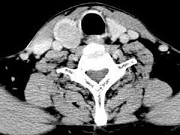

- 单项选择题男,43岁, 右颈部扪及一包块,CT如图所示, 最可能的诊断是 ( )

A、甲状腺腺瘤

B、甲状腺腺癌

C、结节性甲状腺肿

D、甲状腺原发淋巴瘤

E、甲状腺转移瘤